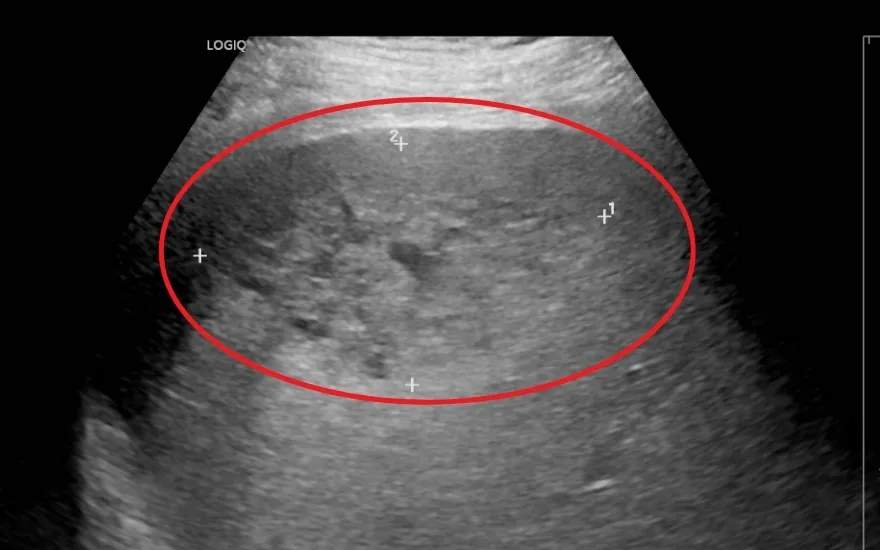

Kết quả siêu âm ổ bụng cho thấy gan của bệnh nhân to bất thường, đặc biệt tại thùy gan phải xuất hiện vùng tổn thương lớn sát bao gan, gồm hai tổn thương chính với kích thước lần lượt là 52×88 mm và 25×32 mm, kèm thâm nhiễm rộng xung quanh. Ngoài ra, bệnh nhân còn có tình trạng dịch ổ bụng và dịch màng phổi.

"Ổ áp xe có kích thước rất lớn, gần như chiếm toàn bộ gan phải, trong khi ranh giới bên ngoài của khối áp xe nằm sát vỏ gan nên nguy cơ chảy máu hoặc vỡ ổ áp xe là rất cao. Đặc biệt, tại thời điểm cấp cứu, tình trạng viêm từ ổ áp xe đã lan thấm ra ngoài, gây tràn dịch màng bụng và tràn dịch màng phổi, khiến diễn biến bệnh trở nên hết sức nghiêm trọng," - PGS.TS.BS Nguyễn Cảnh Bình, Trưởng khoa Tiêu hóa, BVĐK Hồng Ngọc – bác sĩ trực tiếp điều trị cho bệnh nhân H. cho biết.